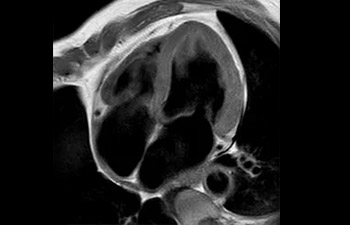

• Baanbrekende versnellingstechniek waarmee niet alleen sequenties versneld worden, maar uw gehele MRI-onderzoek. • Unieke implementatie waarmee 2D- en 3D-scans tot wel 50% sneller gemaakt kunnen worden met een nagenoeg gelijkwaardige beeldkwaliteit.1

• Kan gebruikt worden in alle anatomische contrasten en alle anatomieën.

1 In vergelijking met Philips-scans zonder Compressed SENSE. Resultaten van casestudy's bieden geen voorspellingen voor resultaten in andere gevallen. Resultaten in andere gevallen kunnen variëren.